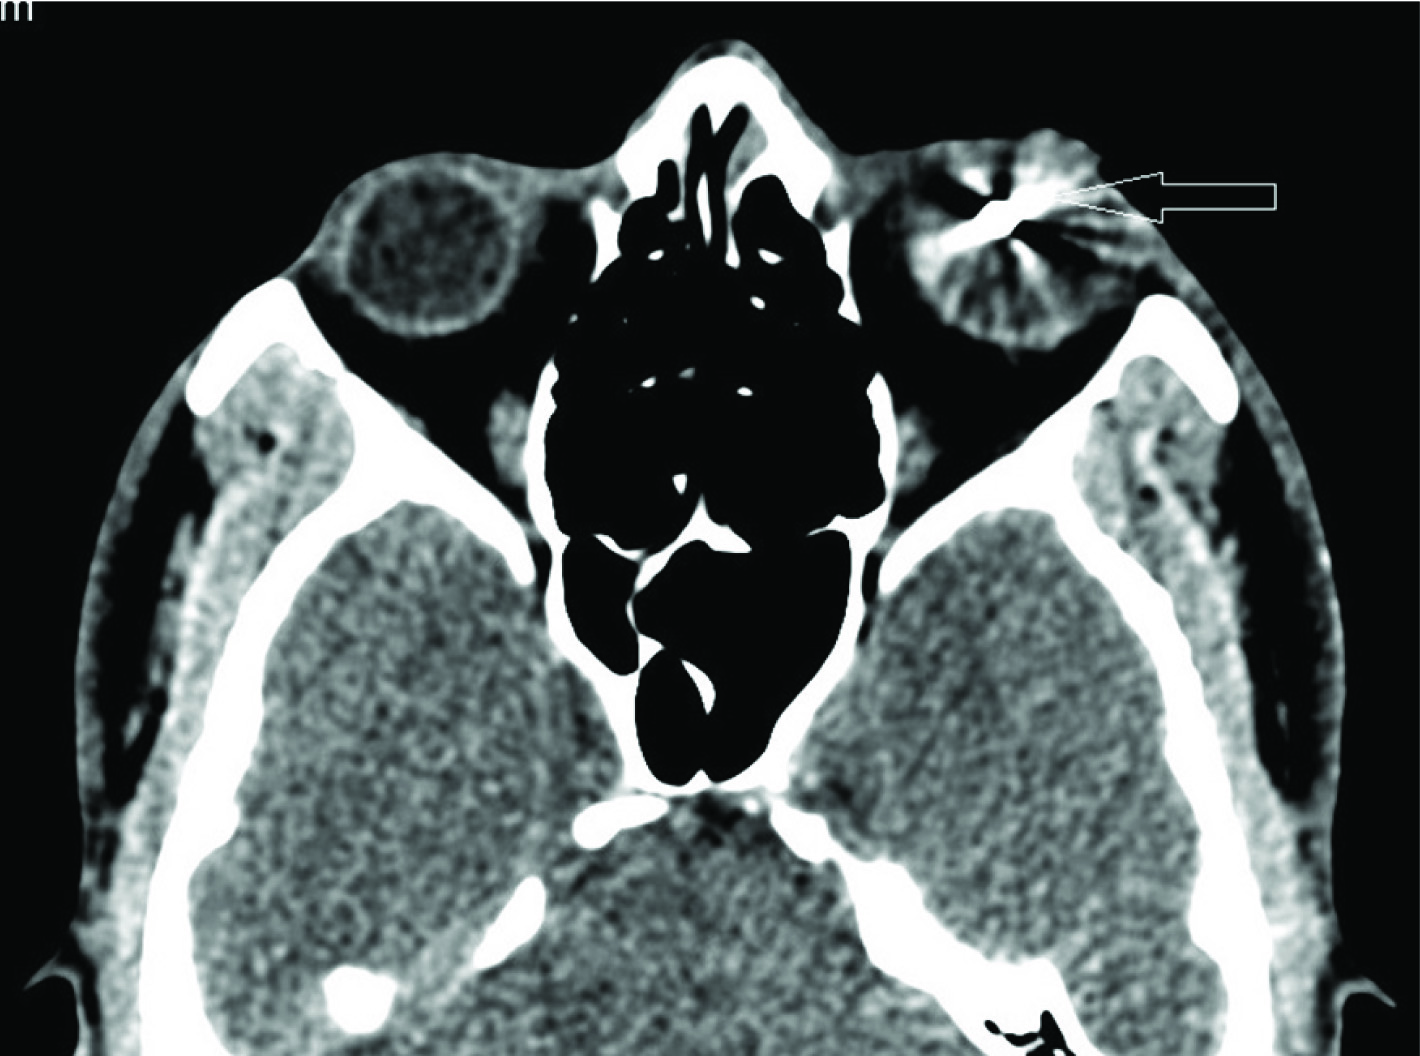

On CT (Computed Tomographic) scan of orbit, imaging was performed using 3 mm slice thickness with contiguous plain axial and coronal scan of orbits was done. A 4.2 (T) x 4.4 (CC) x 3.6 (AP) mm sized Well-defied hyperdense foreign body producing streak artifacts was seen in the posterior chamber of left eyeball. Ill defined mildly hyperdense area was seen in the posterior chamber of left eyeball suggestive of vitreous hemorrhage. Lens of left eyeball was appeared small and distorted. Right eyeball, retro-bulbar area, extra-ocular muscles and bony orbital wall were normal [Table/Fig-2,3,4,5,6].

Axial CT orbit shows a Well-defied hyperdense foreign body producing streak artifacts in the posterior chamber of left eyeball (open white arrow). Right eyeball, retro-bulbar area, extra-ocular muscles and bony orbital wall were normal